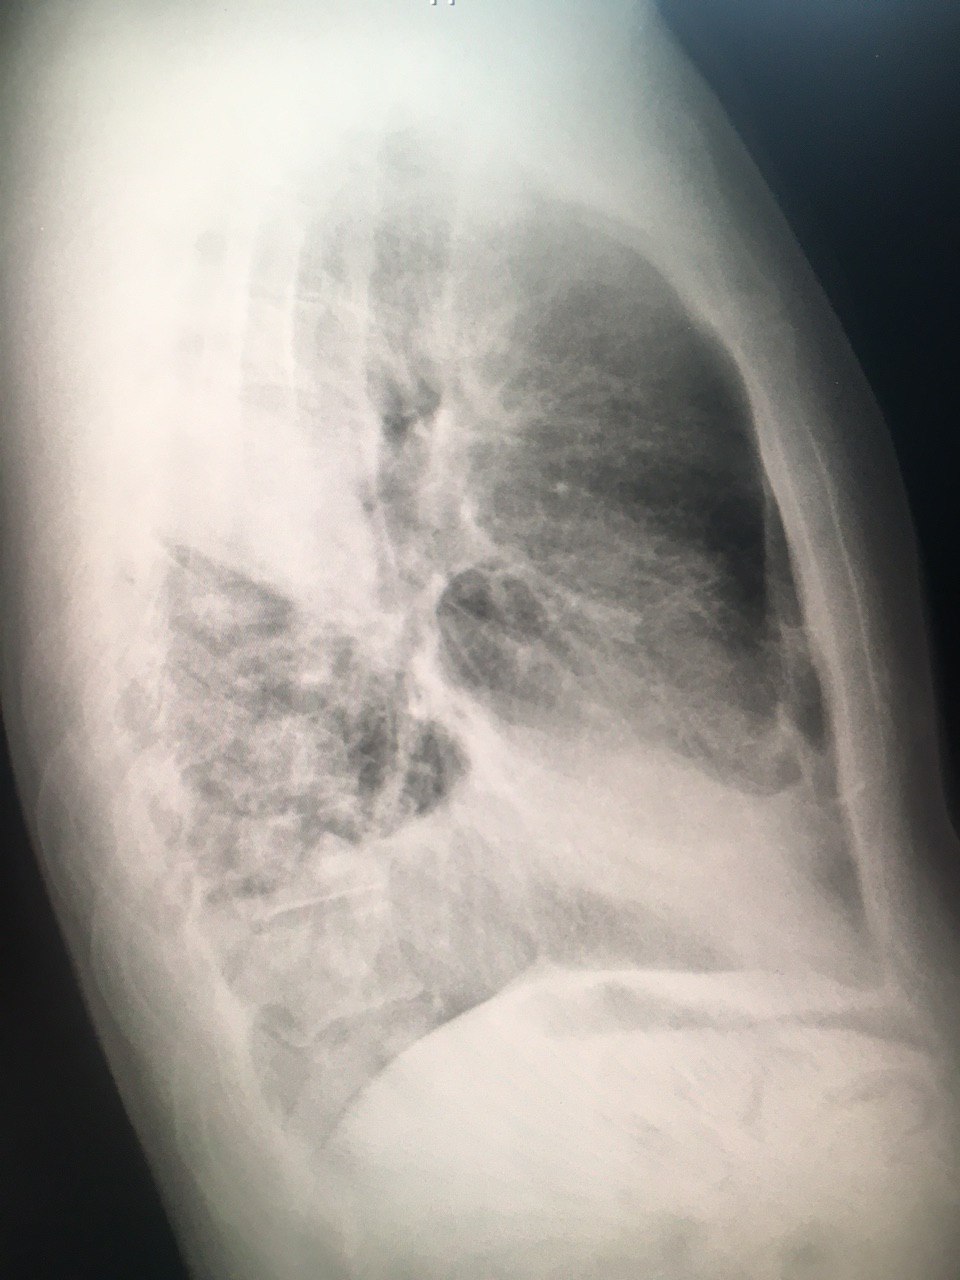

Добрый вечер, коллеги. М, 60 лет. А анамнезе рак правого лёгкого с мтс. Сейчас темп 37.2, кашель с мокротой. Пришли исключить пневмонию.

По-моему нету пневмонии, вы как считаете?

Справа в нижней доле - участок инфильтрации, гидроторакс

S6,S4-5,возмоно выпот ,МСКТ

И все таки пришёл ковид сегодня

Правосторонная плевро пневмония